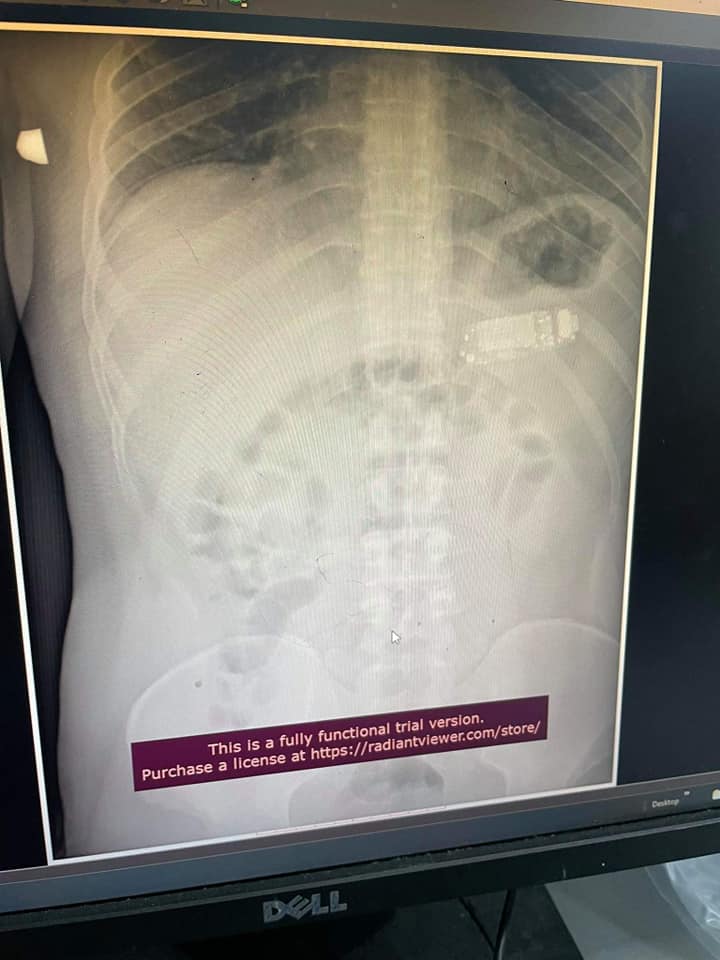

وبعد العملية مباشرة، شارك الدكتور "تيلجاكو" صورًا للهاتف وصورًا بالأشعة السينية والتنظير الداخلي على موقع فيسبوك، حيث يمكن أن نرى بوضوح في الأشعة السينية أن الهاتف في معدته.

وقال الدكتور "سكاندر تيلجاكو" لوسائل الإعلام المحلية في كوسوفو: "تلقيت مكالمة بشأن مريض. قيل لي إنه ابتلع شيئًا ما. وعندما قمنا بالمسح الضوئي، انقسم الهاتف إلى ثلاثة أجزاء في المعدة. كان أحد أجزاء البطارية، وهنا بدأ القلق خاصة إذا بقي لفترة طويلة، كان هناك خوف من حدوث انفجار في المعدة".